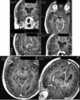

Regenerated rib after resection